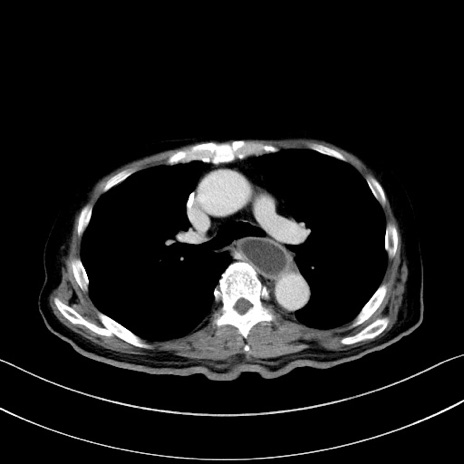

冠状断像